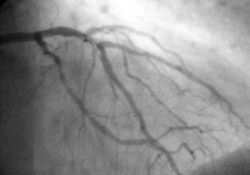

Angiography

In difficult cases or in situations where intervention to restore blood flow is appropriate, coronary angiography can be performed. A catheter is inserted into an artery (usually the femoral artery) and pushed to the vessels supplying the heart. A radio-opaque dye is administered through the catheter and a sequence of x-rays (fluoroscopy) is performed. Obstructed or narrowed arteries can be identified, and angioplasty applied as a therapeutic measure (see below). Angioplasty requires extensive skill, especially in emergency settings. It is performed by a physician trained in interventional cardiology.

Histopathology